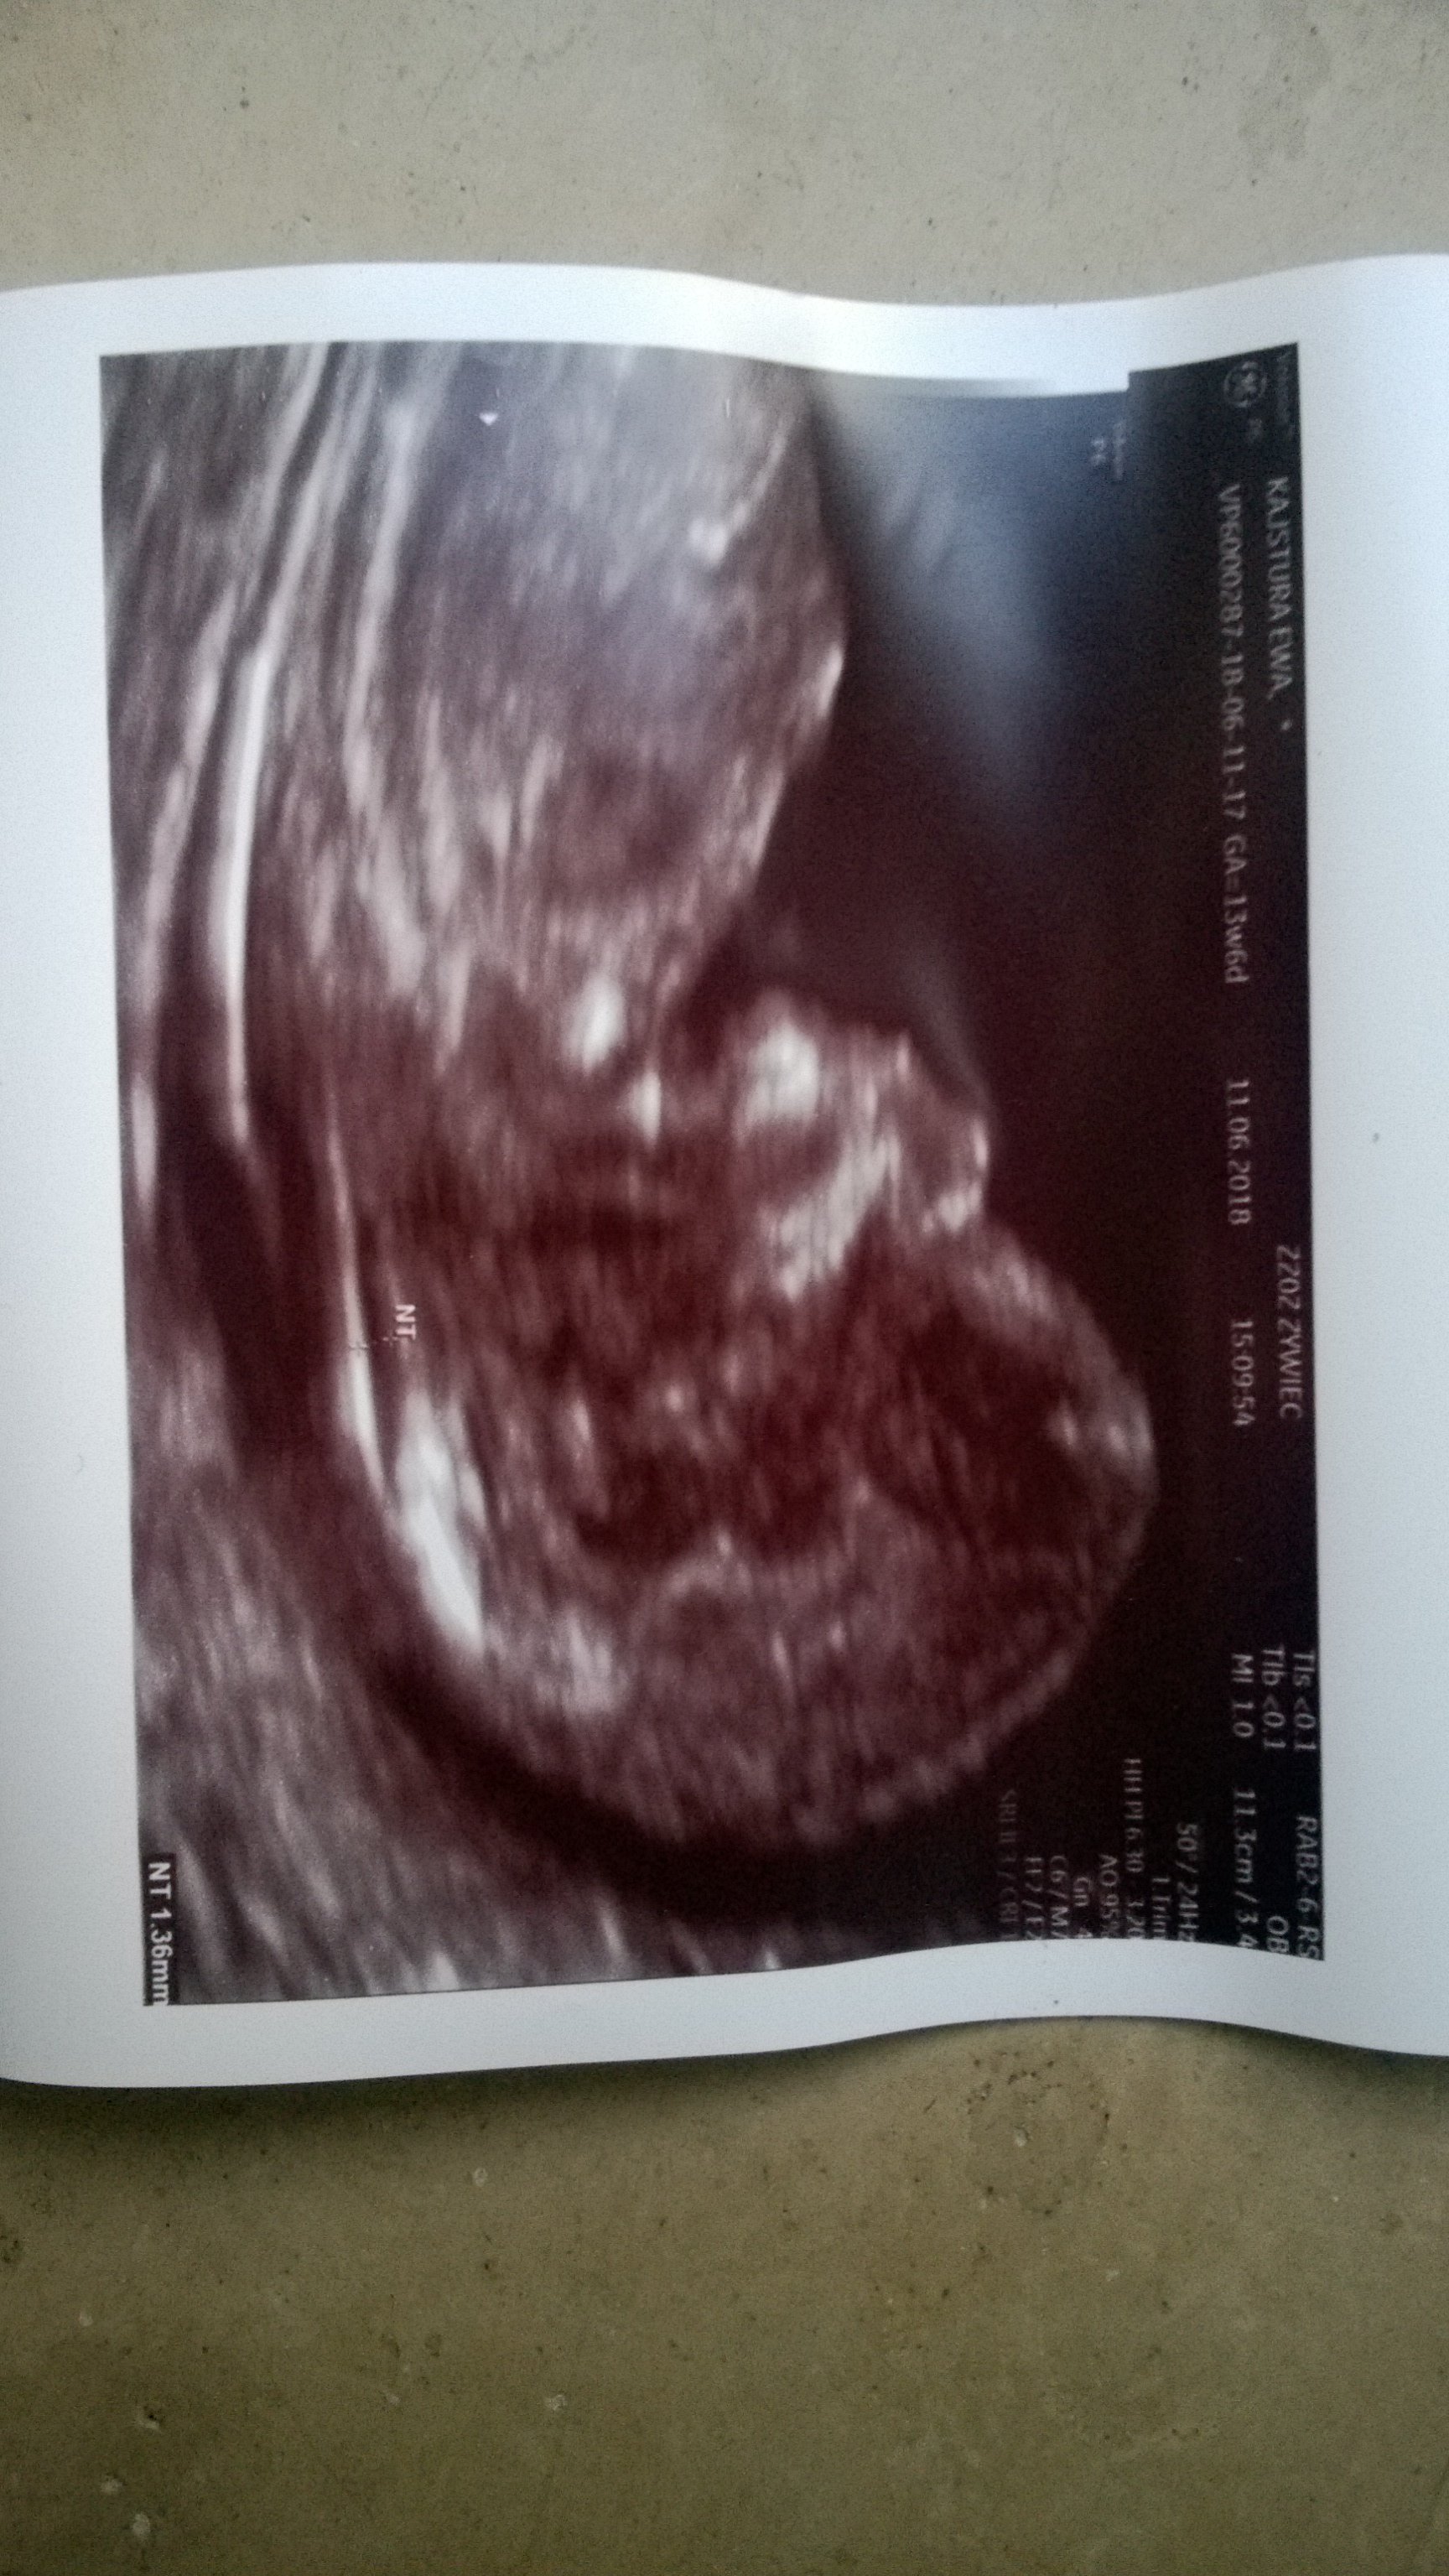

Serduszko pieknie mi bije..

Mama twierdzi, że będe jednak Remek

No i tyle sie dowiedzialam. Dostalam skierowanie na krew bo okazalo sie ze nie ma wszystkiego ☺

Kolejna wizyta 16 lipca ☺

Zobacz załącznik 866827